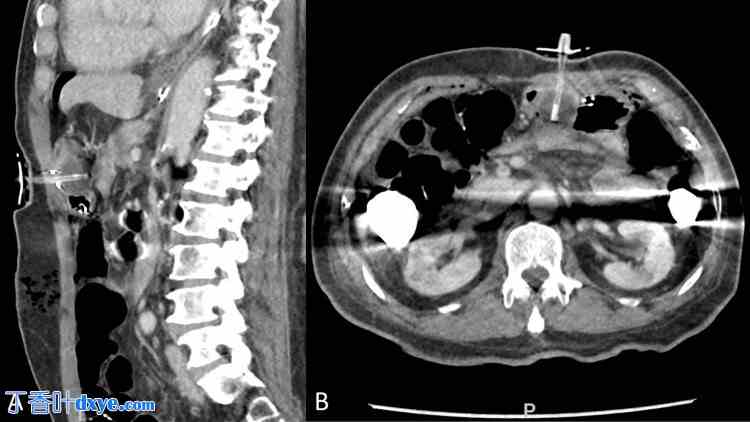

术后第一天,患者夜间出现三次咖啡渣样呕血,无血流动力学不稳定,白细胞增多至18,000/微升。患者无发热,心动过速,心率为100-120次/分钟。体格检查显示,手术部位清洁,无出血或感染的外部征象。患者开腹手术和胃管置入处周围疼痛,无腹胀或腹膜炎征象。由于胃肠道出血和白细胞增多,患者进行了腹部非造影CT扫描,结果显示腹腔内多处小气灶,脐周区域有手术性改变,胃部接近腹前壁,这可能与腹腔镜介入治疗相符。胃造瘘管似乎终止于远端胃体。此外,胃造瘘管置入处前后胃壁完全贴合,胃部似乎被压迫在球囊和腹壁之间(图1)。后一种情况未能立即发现,患者请胃肠科会诊,进行内镜评估并治疗呕血。

图 1. 计算机断层扫描 (A) 矢状面和 (B) 横断面/轴向图像显示腹腔镜胃造瘘管经胃前后壁置入术后的变化。